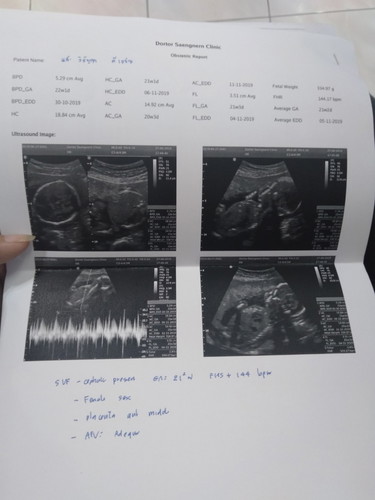

21w 6d

ลุ้นจากรพ.มาแล้วไม่รู้เพศ ซาวคลีนิคเลย ลูกสาวจ้าาา...สมใจหวัง ย่ารักย่าหลงเลยทีนี้??